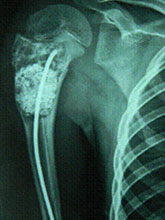

Unicameral Bone Cyst (UBC) or Simple Bone Cyst (SBC)

Unicameral Bone Cyst (UBC) or Simple Bone Cyst (SBC) constitutes 3 % of all bone tumours.

Cyst that Require treatment

Treatment Modalities

About Bone Cyst Bone Cyst is a curable condition. Spontaneous resolution after a fracture is known. Success rate with Intra-Lesional Steriod and Bone Marrow is about 80%. Currettage, bone grafting and intra-lesional rodding with titanium implants or screws have over 90 % success rate in curing the lesion.